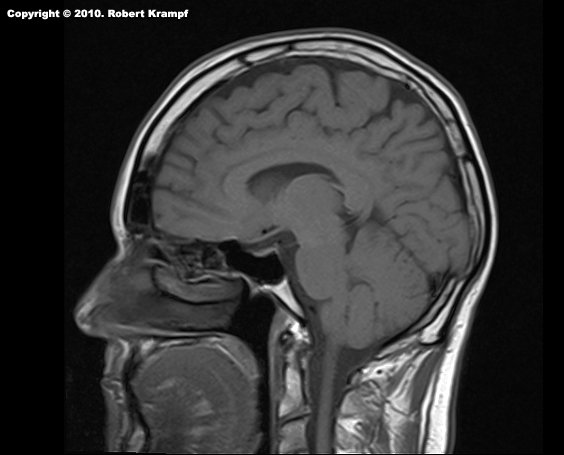

How much radiation exposure do you get from a CAT scan? (Yes, this is me, and yes, this is actually an MRI, but I did not have a CAT scan, so this will have to do.)

Depending on the area for the CT scan, and the number of "slices", the radiation exposure can be from 1-10 millisieverts. A dose of 1000 millisieverts (one sievert) can cause radiation sickness. At Chernobyl, the radiation exposure was up to 6000 millisieverts per hour.